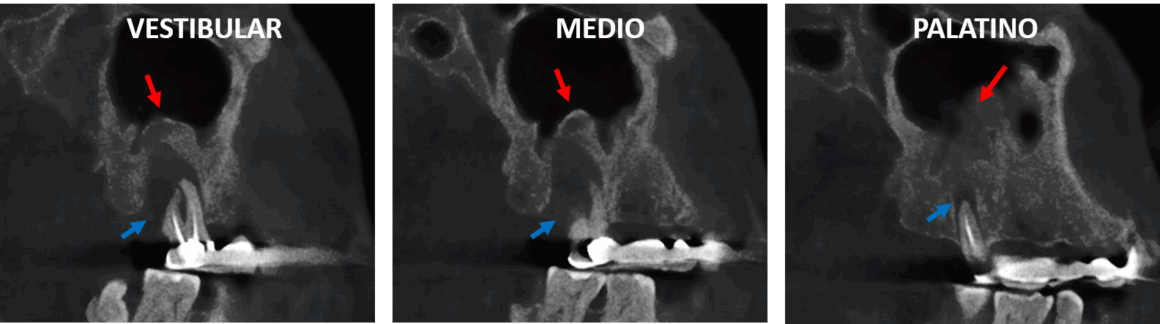

Fig.1

En la evaluación con tomografía computarizada cone beam, en cortes sagitales (Fig.1) se observa el órgano dentario 27 con material de obturación de conductos parcial con una lesion osteolítica amplia que compromete la mayor parte del soporte óseo dentario y condiciona el desplazamiento del piso del seno maxilar compatible con osteoperiostitis periapical.